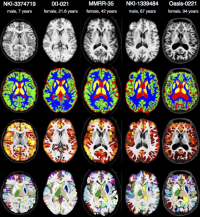

Interdisciplinary Bachelor/Master thesis in the domain of "Atlas Generation"

Within this project, clinically acquired magnetic resonance imaging (MRI) brain data of the past years is processed retrospectively. Using these data the primary task is to create a brain template with the Advanced Normalization Tools (ANTs) which will serve as a reference in diagnosis in neurodegenerative and psychiatric diseases. Beyond this, further tasks may vary depending on the individual skillset and type of work.